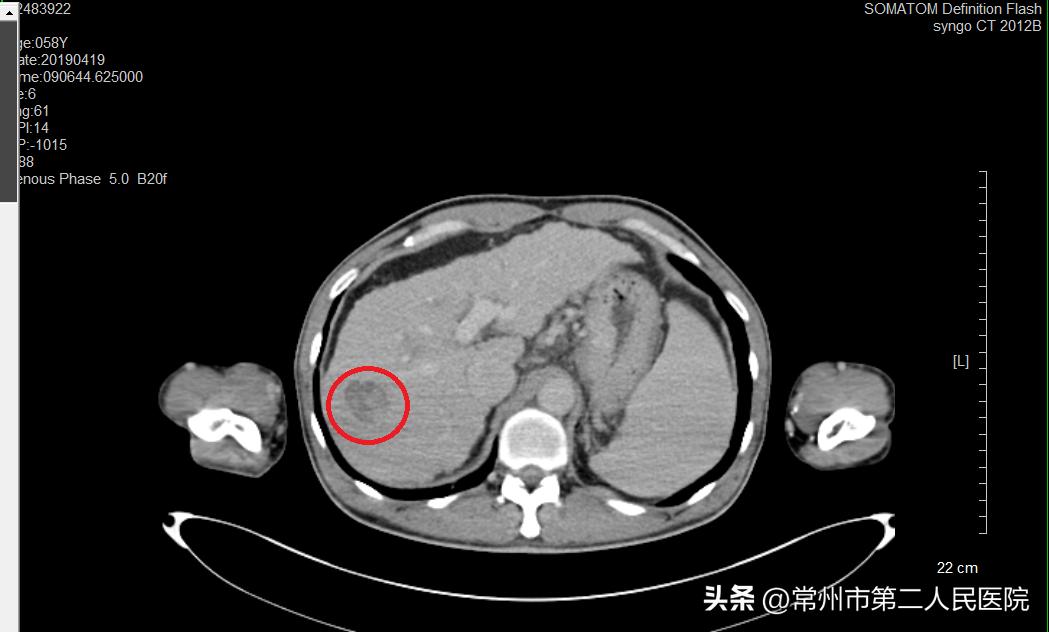

▲术前

“像姚先生这样的病例,过去治疗方法包括肝切除术、全身静脉化疗,现在介入治疗成为部分肝癌首选治疗方法。治疗过程中,我们将一根铅笔芯粗细的消融针,在CT引导下穿刺入肿瘤内,外接消融治疗仪,以90℃以上的温度直接将肿瘤组织碳化灭活。治疗5cm以内的原发性肺癌、原发性肝癌可达到与手术切除相当的治疗效果;对于肺、肝转移性癌进行部分或完全灭活可起到减轻患者肿瘤负荷、延长生存时间、提高生活质量的效果。由于治疗时间短,患者的损伤小,术后2-3天就可以出院恢复正常生活。”